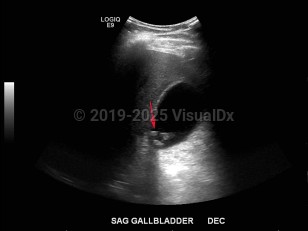

Imaging Studies image of Biliary calculus - imageId=7878647. Click to open in gallery.  caption: '<span>Ultrasound of the right upper  quadrant demonstrating echogenic foci with shadowing in the gallbladder  consistent with cholelithiasis.</span>'

Ultrasound of the right upper quadrant demonstrating echogenic foci with shadowing in the gallbladder consistent with cholelithiasis.